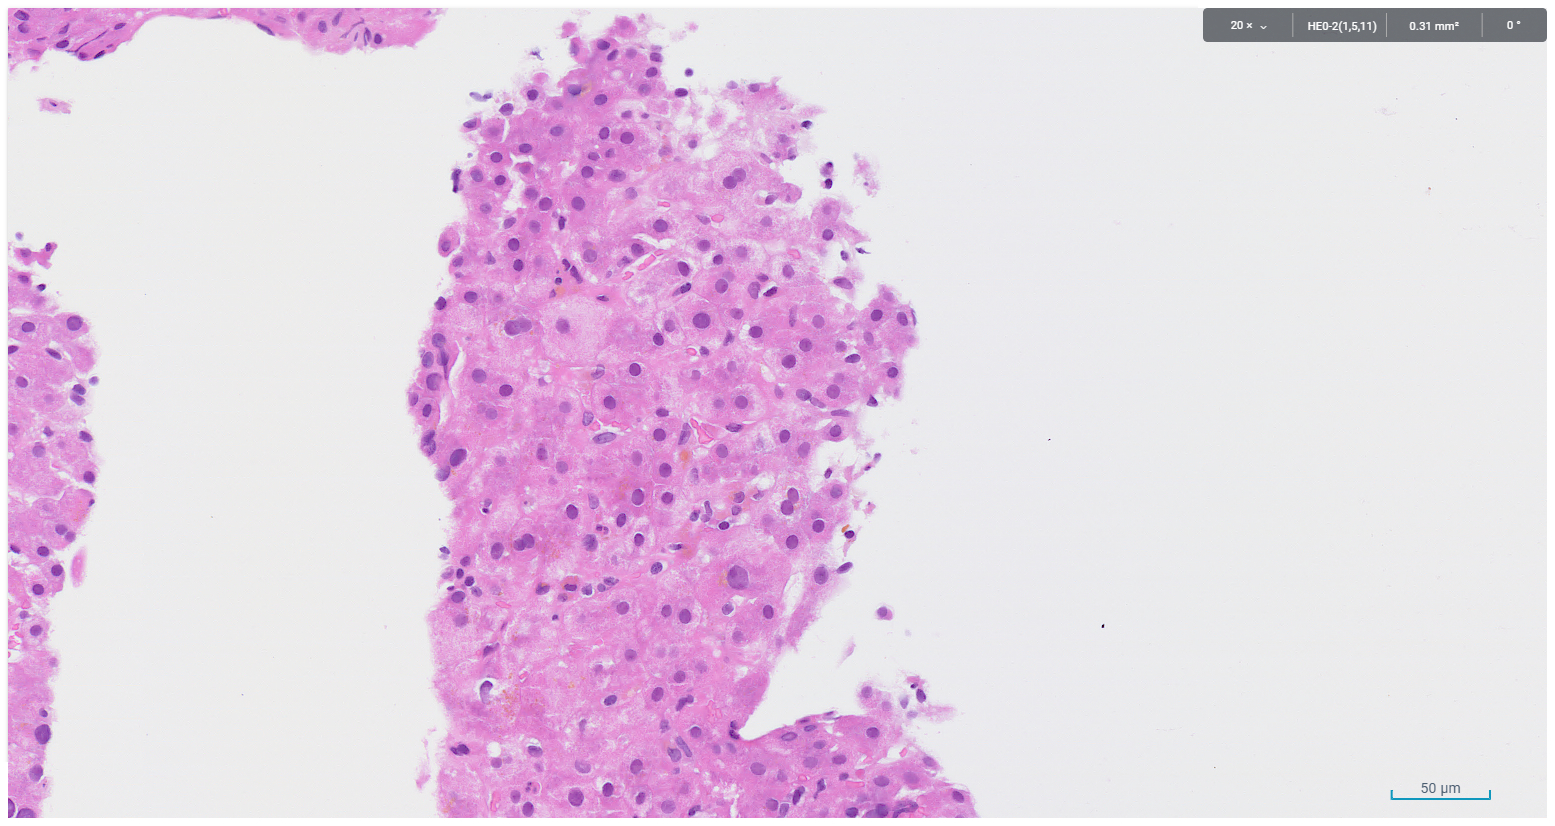

A core biopsy taken from the right hepatic lobe showed periportal chronic inflammation without a prominent plasma cell component, and focal interface activity (Figure 1). Mild bile ductular proliferation and mild periportal fibrosis were noted and highlighted with CK7 immunohistochemistry (Figures 2 and 3). There was no evidence of bile duct injury or ductopenia. The hepatic lobules contained scattered chronic inflammatory infiltrate and mild canalicular cholestasis (Figures 4 and 5). Steatosis, confluent necrosis, Mallory-Denk bodies and granulomata were not identified.

Figure 4. Canalicular cholestasis and scattered lobular lymphocytic infiltrate

Figure 5. Canalicular cholestasis and scattered lobular lymphocytic infiltrate